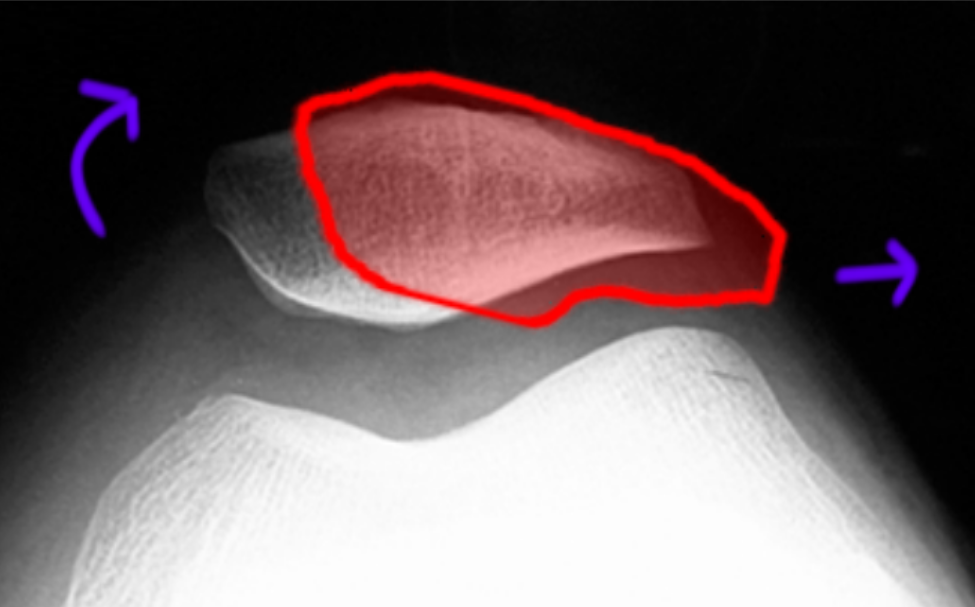

Diagrams and radiographs illustrate preoperative patellar tilt and What Does A Lateral Patellar Tilt Mean lateral patellar compression syndrome is the improper tracking of the patella in the trochlear groove generally caused by a tight lateral. lateral patellar tilt is often influenced by several anatomical and structural factors that can contribute to. This is when the patella tilts slightly outwards so it can’t sit flat in the groove and therefore rubs against the. What Does A Lateral Patellar Tilt Mean.